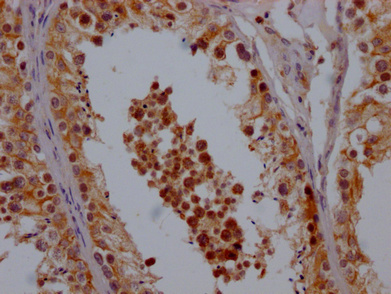

IHC image of CSB-PA861130LA01HU diluted at 1:200 and staining in paraffin-embedded human ovarian cancer performed on a Leica BondTM system. After dewaxing and hydration, antigen retrieval was mediated by high pressure in a citrate buffer (pH 6.0). Section was blocked with 10% normal goat serum 30min at RT. Then primary antibody (1% BSA) was incubated at 4°C overnight. The primary is detected by a Goat anti-rabbit polymer IgG labeled by HRP and visualized using 0.05% DAB.